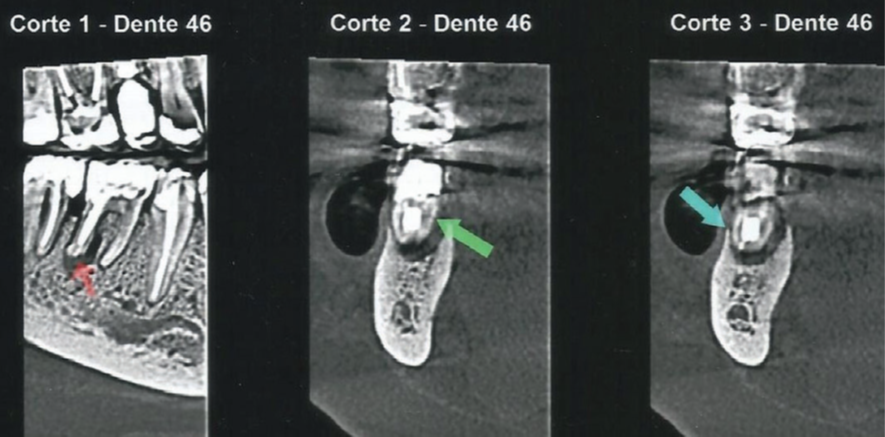

No exame clínico, a sondagem periodontal mostrou 7 mm de profundidade na distal do dente 46, com sangramento à sondagem. Para complementar o diagnóstico, a radiografia periapical do dente 46 apontou uma extensa lesão radiolúcida na raiz distal que apresentava conduto obturado, e a tomografia computadorizada de feixe cônico (TCFC) permitiu a visualização de uma tênue linha hipodensa oblíqua no terço médio da raiz distal, com aspecto sugestivo de trinca/fratura radicular (Figuras 1 e 2).